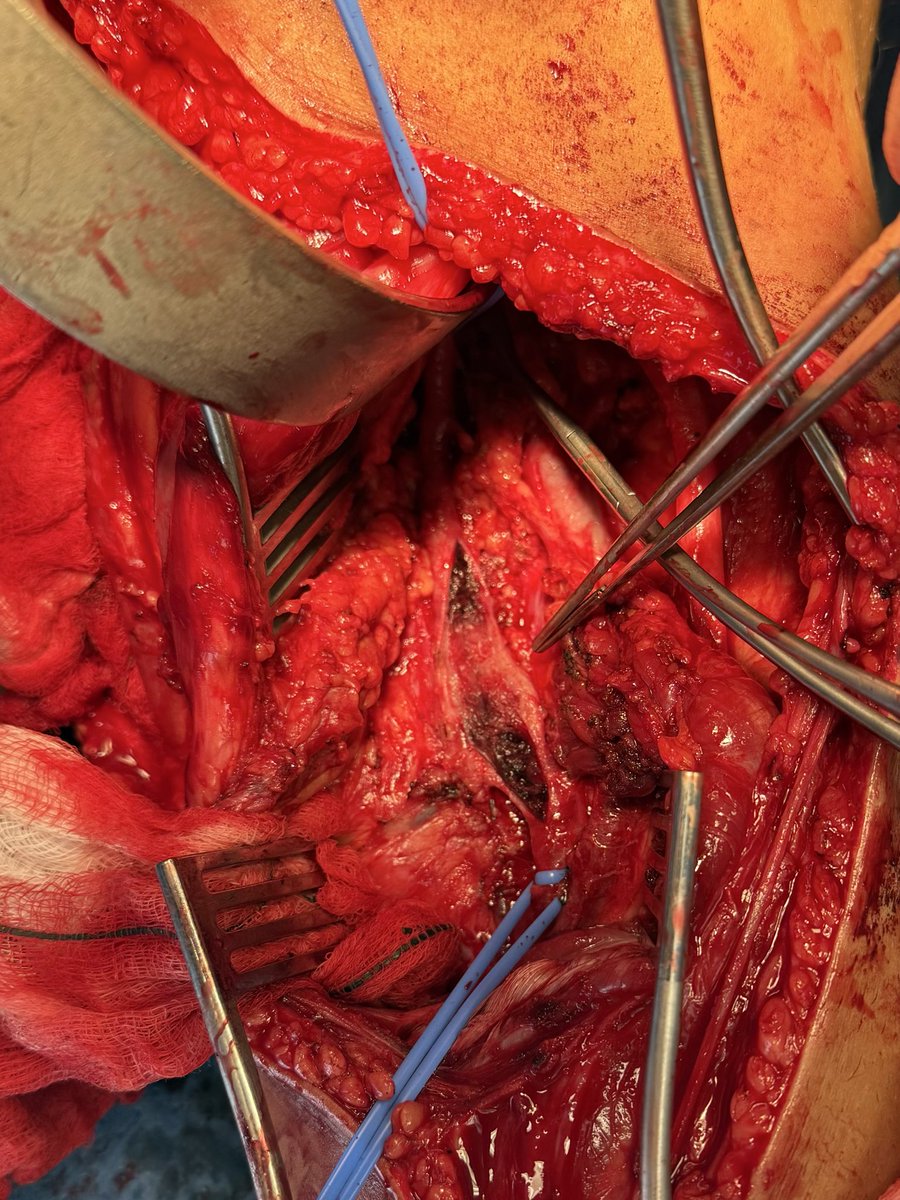

Diagnosis : Popliteal artery entrapment syndrome causing acute limb ischemia Intra-op pictures

#vasctwitter 17 yrs old male, keen football player.sudden onset pain in right leg and foot. Absent foot pulses and pale foot. CTA below. What is the diagnosis? Look at cross sectional image?! How would you treat?